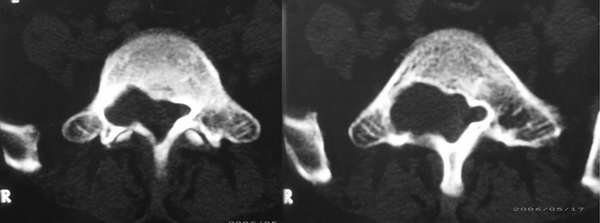

患者,女性,60岁。腰痛、腿痛一周余,临床医生考虑:椎间盘突出,行ct及mr检查

骶骨椎体层面囊性占位,骶孔不扩大。考虑蛛网膜囊肿。

征象:1、骶椎管偏右侧囊性病变,长t1长t2改变,均匀。2、慢性病变过程,邻近骨质有吸收变薄。

考虑:盲囊蛛网膜囊肿。

S1椎长T1长T2信号,与蛛网膜下腔相连,边界清晰,CT可见局部骨质吸收,边缘硬化改变。支持骶管囊肿。